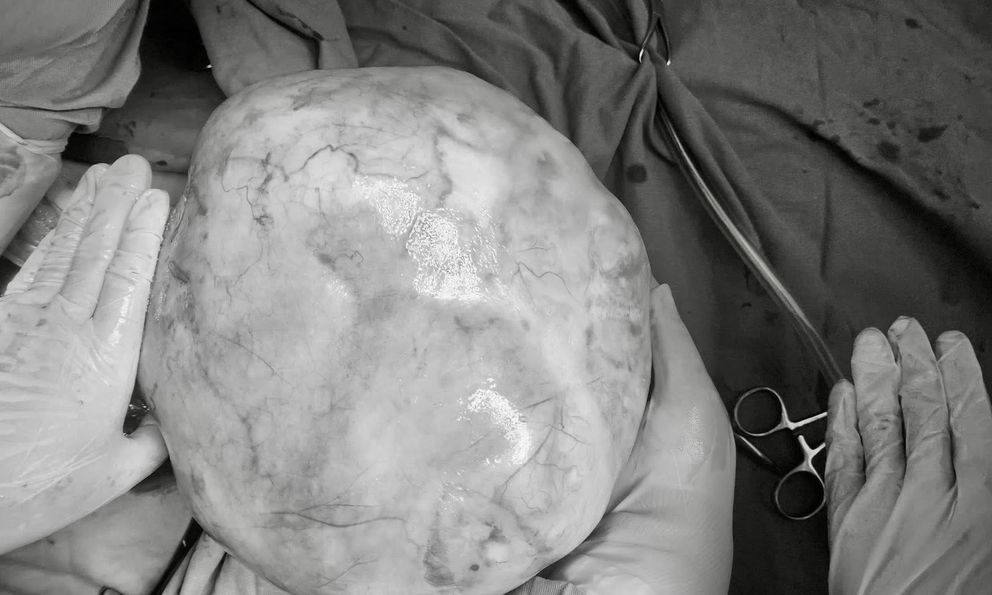

Mới đây, một ca bệnh hy hữu đã được ghi nhận tại Bệnh viện Phụ Sản Trung ương khi tiếp nhận bệnh nhi 14 tuổi mang khối u khổng lồ nặng tới 4,3kg.

Kết quả chẩn đoán hình ảnh cho thấy một khối u lớn xuất phát từ buồng trứng phải, nghi ngờ là u tế bào mầm ác tính, là nhóm bệnh lý thường gặp ở lứa tuổi nhi khoa. Không dừng lại ở đó, buồng trứng trái của cô bé cũng xuất hiện thêm một khối u bì lành tính kích thước 8cm. Đây là một thách thức lớn đối với ê-kíp phẫu thuật vì bệnh nhi còn quá trẻ, mục tiêu đặt ra không chỉ là loại bỏ khối u mà còn phải bảo tồn tối đa chức năng nội tiết và sinh sản.

TS.BS Nguyễn Văn Thắng, người trực tiếp chỉ huy ca mổ, nhấn mạnh việc lấy trọn khối u nguyên vẹn là yếu tố sống còn. Nếu khối u ác tính bị vỡ trong lúc thao tác, các tế bào ung thư sẽ lan tràn khắp ổ bụng, buộc bệnh nhi phải đối mặt với các đợt hóa trị nặng nề sau đó.

May mắn là nhờ sự nỗ lực của đội ngu y bác sĩ, ca phẫu thuật đã thành công rực rỡ khi khối u 4,3kg chứa đầy tóc, răng và xương được bóc tách hoàn toàn. Đồng thời, phần tổ chức lành bên buồng trứng trái cũng được giữ lại, đảm bảo tương lai làm mẹ cho bé gái sau này.